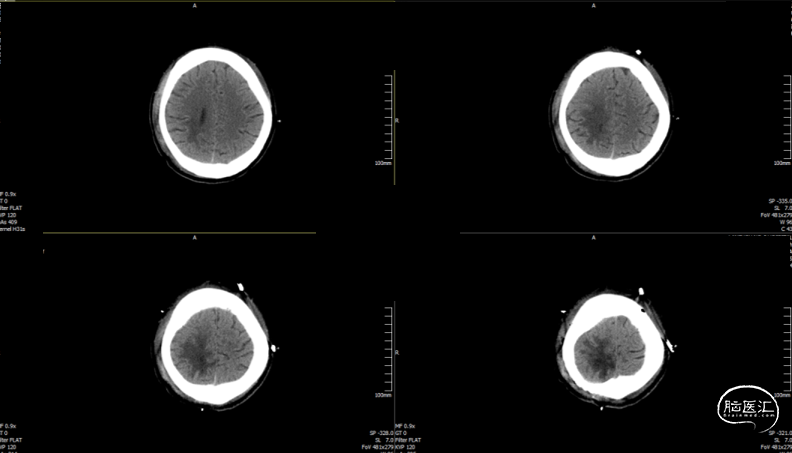

术后随访

术后CT

术后随访

术后72h CT,复查后拔除硬膜下引流管

术后72h胸部 CT

术后1周 CT

术后70天CT